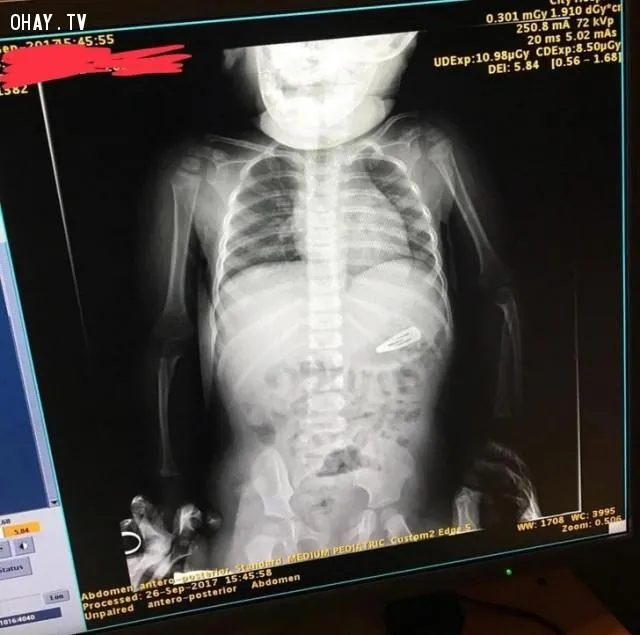

Ничего удивительного! Просто девочка отказалась делать снимок без своей любимой игрушки – свинки Пеппы

Фото imgur